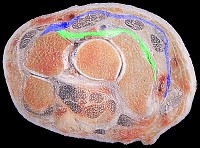

Normal relationship of the dorsal intercarpal ligaments (green) and extensor retinaculum (blue) at the level of the triquetrum. (image modified from Zancolli E A, Cozzi E P 1992 Atlas of Surgical Anatomy of the Hand. Churchill Livingstone, Edinburgh.)

Click for larger image